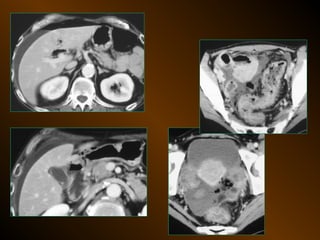

• X QUANG CẮT LỚP ĐIỆN TOÁN

– Mật độ

– Vị trí

– Nguyên nhân

TỤ DỊCH KHU TRÚ

• X QUANG QUY ƯỚC

• SIÊU ÂM

– Mật độ, bắt cản quang ?